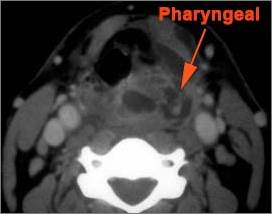

9 month old male presenting to the emergency room with poor feeding, fever, respiratory distress and possible retropharyngeal abscess or suppurative retropharyngeal adenitis.Exam

There is excessive enhancement or thickening of the mucosa or hypertrophy of the lymphoid tissue in the nasopharynx. |

Yes | NA |

There is edema within the fat of the adjacent parapharyngeal space. |

There is edema within the fat of the adjacent retropharyngeal space. |

Pharyngitis with suppurative retropharyngeal adenitis.